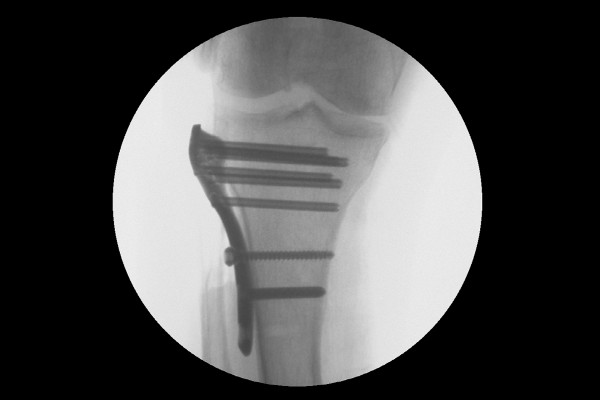

수술은 실시간 X-RAY인 C-ARM으로 확인하면서 진행합니다. 먼저 수술부위가 어긋나지 않게 골절된 무릎 경골 고평부를 리덕션 포셉(Reduction Forceps)이라는 수술기구로 잡고서, 금속판을 임시로 위치시킵니다.

2f992d7239a97edca630fa072198310c_1766717662_9805.jpg